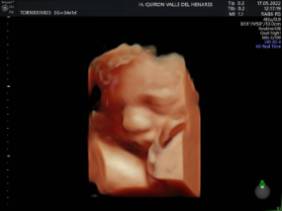

El Hospital Quirónsalud Valle del Henares ofrece la posibilidad de realizar ecografías gestacionales 5D. Este tipo de exploración permite obtener una imagen muy realista del bebé y se puede realizar en cualquier etapa de la gestación -aunque lo recomendado es realizarla entre las semanas 28 y 32 de gestación, ya que técnicamente es el mejor momento y es mucho más probable obtener imágenes de buena calidad-.

La exploración tiene una duración aproximada de 30 minutos en los que los padres y los familiares que ellos decidan (se permite el paso de hasta 3 acompañantes, dada la situación epidemiológica actual) pueden disfrutar de ver a su bebé en una pantalla de gran formato.

"Realizar esta ecografía con nuestro equipo de diagnóstico prenatal tiene un valor añadido -señala la Dra. Rocío Vellido Cotelo, Jefa Asociada de Ginecología y Obstetricia del Hospital Quirónsalud Valle del Henares, dado que quien realiza la prueba es un especialista en la materia, siempre se completa la exploración con un examen morfológico y de perfil biofísico fetal, que permita valorar el estado de bienestar del bebé más allá de la captura de videos y fotografías".